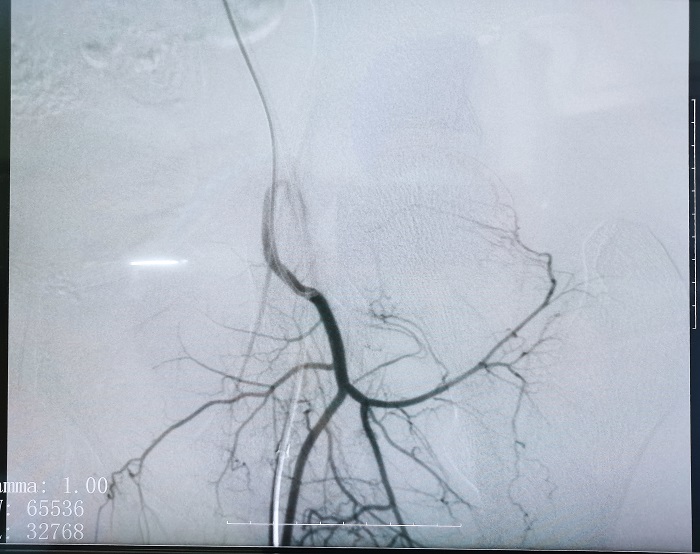

普愛平板介入中C在FTE手術(shù)過程中拍攝的造影圖像

若根據(jù)HSG的診斷,患者存在輸卵管積水,則可行輸卵管栓塞術(shù)(Fallopian tube embolization, FTE),通過介入手段,注入栓塞劑或使用彈簧圈等器材進(jìn)行栓塞,可以有效地阻斷輸卵管內(nèi)的血流和組織,從而治療輸卵管積水。這個(gè)過程通常是在X線或超聲引導(dǎo)下進(jìn)行的,可以清楚地看到輸卵管的情況。

輸卵管栓塞的介入治療作為輸卵管積水的預(yù)處理是一項(xiàng)創(chuàng)新性的方法,也是行之有效的方法,所有操作都可在醫(yī)學(xué)影像設(shè)備下進(jìn)行,定位準(zhǔn)確、操作簡(jiǎn)便。同時(shí)因?yàn)榛臼俏?chuàng)手術(shù),所以對(duì)卵巢功能無影響,可以有效改善輸卵管積水引起的癥狀,如腹痛、腹脹等,并提高患者的生育能力,對(duì)體外受精-胚胎移植(IVF-ET)的發(fā)展有新的突破,妊娠率有顯著性增加。